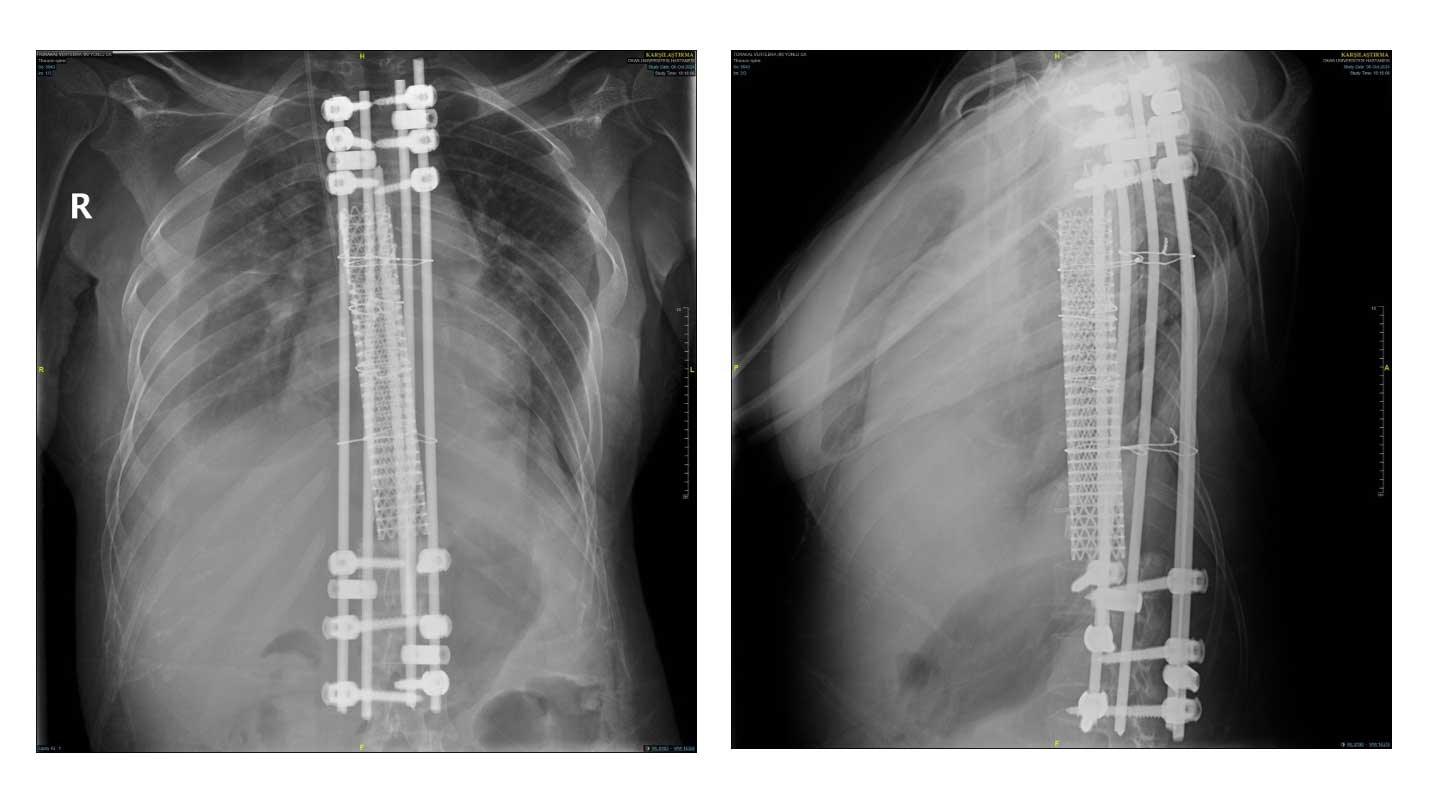

Ameliyat Sonrası: Röntgende korpektomi sonrası fibula, cage ve enstrümentasyon uygulaması görülmekte.